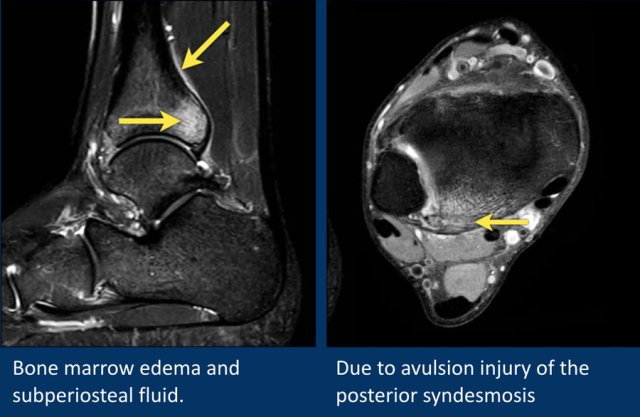

This patient has bone marrow edema on the posterior side of the distal tibia.

On the axial image, the edema is localised around the insertion site of the posterior syndesmosis.

This is edema due to a ligamentous avulsion injury.